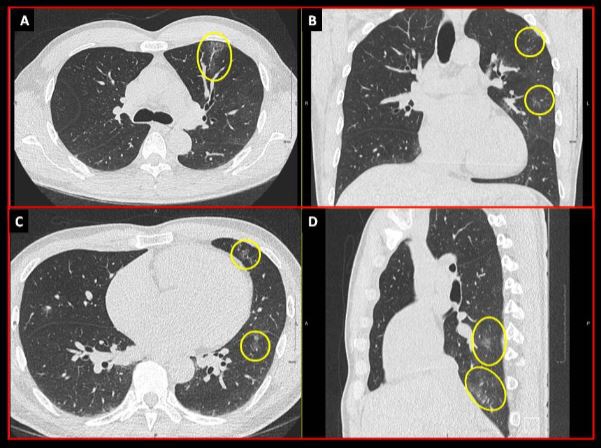

Ground glass opacities observed on X-ray image.

Sur cette radiographie thoracique, on peut voir de minuscules « opacités en verre dépoli », encerclées en jaune. Ces taches grises et floues ne masquent pas les autres structures sur un tomodensitogramme. Les scientifiques croient qu’elles pourraient indiquer la présence d’une pneumonie liée à la COVID-19 ou d’une inflammation des poumons causée par l’infection virale.